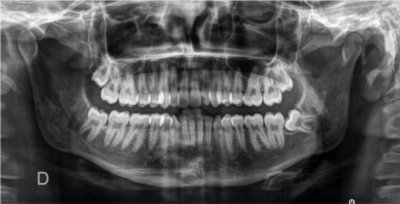

Images de panoramiques dentaire:

-pour le panoramique dentaire l'appareil tourne autour de vous, votre tête est installée dans l’appareil et maintenue par un système de contention. Une pièce en plastique sera placée entre vos dents de manière à ce que vous mâchoires soient légèrement écartées. L’acquisition du cliché dure environ 10 à 20 secondes durant lesquelles vous devez rester immobile.

- C’est un examen extrêmement fréquent chez les enfants qui ont des problèmes orthodontiques.

Cet examen est fait le plus souvent chez l’enfant dans les bilans d’orthodontie.

Le cone beam dentaire est par exemple indiqué dans les pathologies suivantes :

- dents incluses, surnuméraires